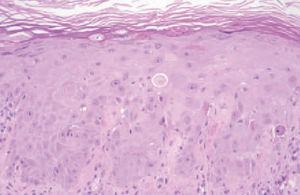

Fig. 2.Destaca una epidermis con ausencia relativa de núcleos, alteraciones madurativas de los queratinocitos y ocasionales queratinocitos necróticos. (Hematoxilina-eosina, ×100.)

En las determinaciones analíticas destacaba pancitopenia (leucocitos, 1.940; hemoglobina, 12,6 g/dl; plaquetas, 3.000), aumento de las enzimas hepáticas (transaminasas glutamicooxalacética [GOT], 54; glutamicopirúvica [GPT], 85; y gammaglutamiltranspeptidasa [GGT] 136) y proteínas totales de 5,7 g/dl. En el aspirado de médula ósea existían signos de toxicidad por metotrexato, consistentes en una médula ósea hipocelular con megacariocitos disminuidos y cambios megaloblásticos de la serie eritroide y granulocítica, con algún blasto ocasional e histiocitosis y plasmocitosis reactiva. La biopsia de una de las lesiones eritema-tosas violáceas de la pierna derecha mostraba una epidermis constituida por células de citoplasma amplio, con ausencia relativa de núcleos, importantes cambios madurativos, imágenes de atipia celular y algunas mitosis (fig. 2). Asimismo se observaba una discreta degeneración hidrópica vacuolar de la capa basal y escasos infiltrados inflamatorios linfocitarios de distribución perivascular. Focalmente se encontraban imágenes de metaplasia escamosa en los conductos ecrinos. Se suspendió el metotrexato y se instauró tratamiento con ácido folínico, imipenem y factor estimulante de colonias de granulocitos (G-CSF), con rápida mejoría clínica y analítica. Posteriormente el paciente ha presentado nuevos brotes de psoriasis, pero no se ha reintroducido el metotrexato.